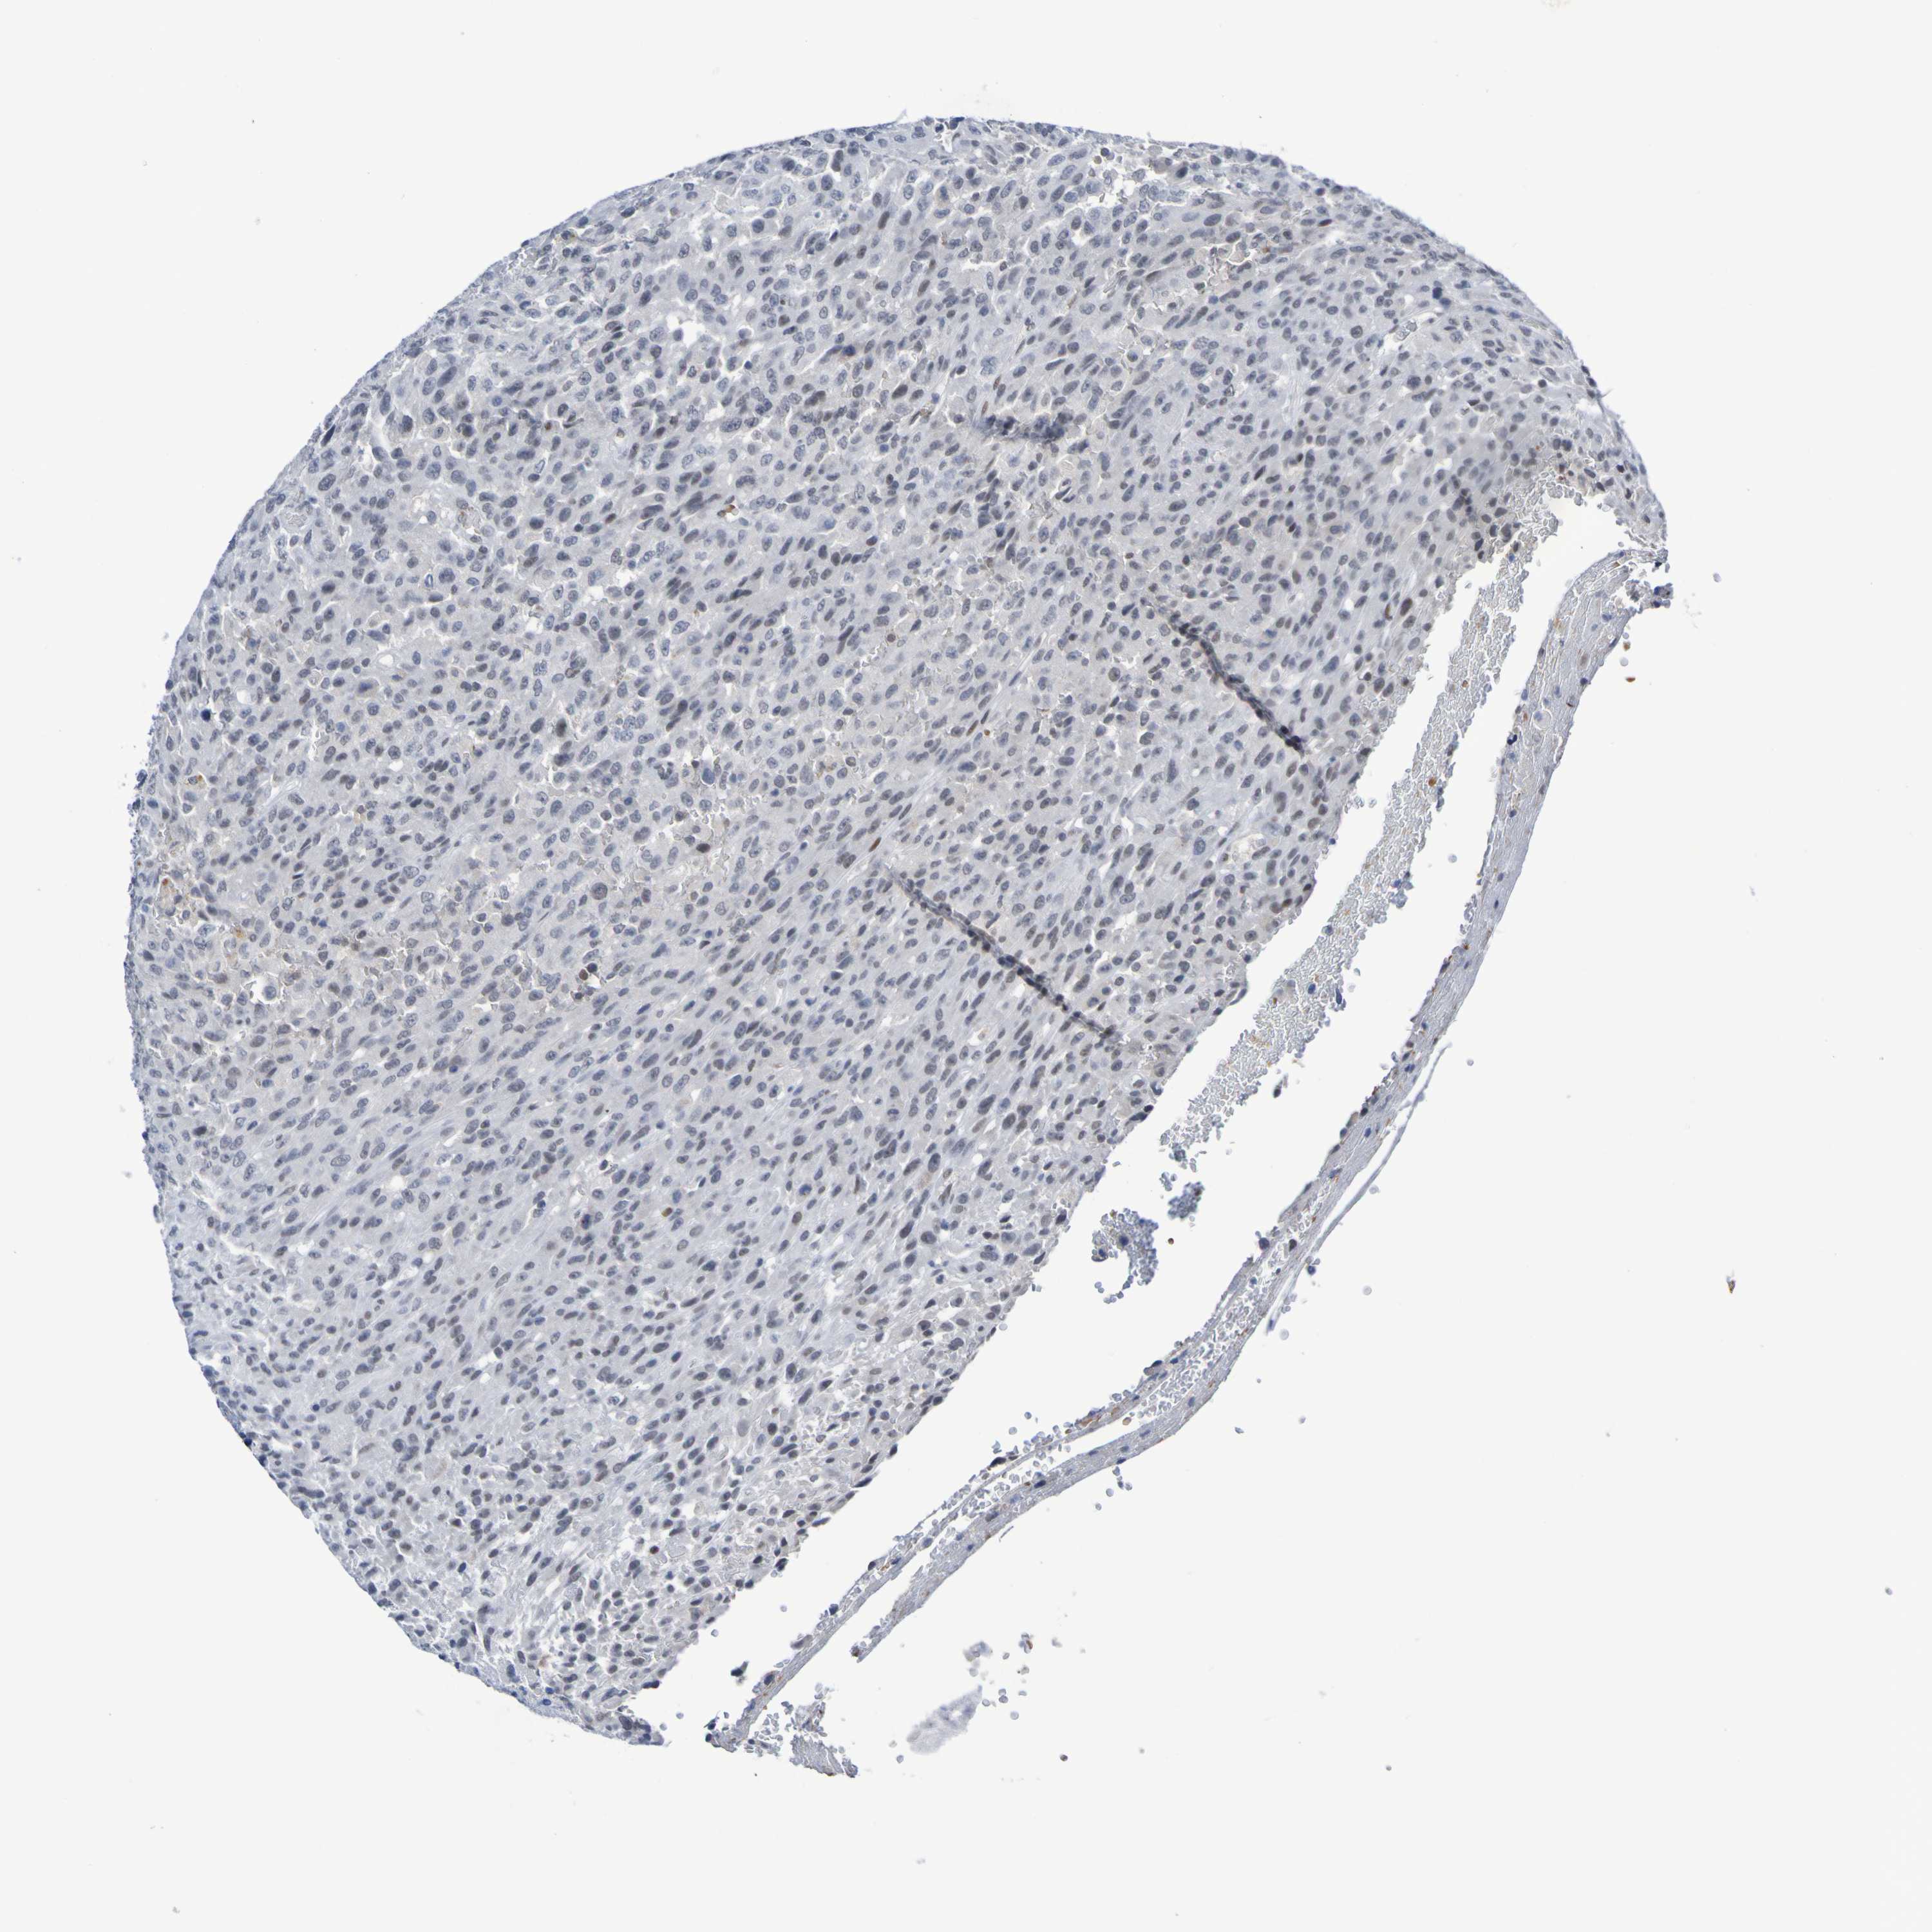

UROTHELIAL CANCER - Protein expressioni

A mouse-over function shows sample information and annotation data. Click on an image to view it in a full screen mode. Samples can be filtered based on level of antibody staining by selecting one or several of the following categories: high, medium, low and not detected. The assay and annotation is described here.

Note that samples used for immunohistochemistry by the Human Protein Atlas do not correspond to samples in the TCGA dataset.

Antibody stainingi

Antibody staining in the annotated cell types in the current human tissue is reported as not detected, low, medium, or high, based on conventional immunohistochemistry profiling in selected tissues. This score is based on the combination of the staining intensity and fraction of stained cells.

Each image is clickable and will lead to virtual microscopy that enables deeper exploration of all samples and also displays staining intensity scores, fraction scores and subcellular localization as well as patient and tissue information for each sample.

Antibody HPA011356

Staining

High

Medium

Low

Not detected

Intensity

Strong

Moderate

Weak

Negative

Quantity

>75%

75%-25%

<25%

None

Location

Nuclear

Cytoplasmic/membranous

Cytoplasmic/membranous,nuclear

Urothelial carcinoma, Low grade

Urothelial carcinoma, High grade